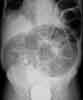

You order an abdominal radiograph. What abnormality does this filmreveal, and what further workup is required to arrive at a diagnosis?

Elderly man with sudden, severe abdominal pain: Thesupine radiograph reveals a very large dilated loop of bowelin the upper abdomen that has a "coffee bean" shape(A, white arrow). On close inspection, this loop has haustralmarkings, which identify it as colon. In addition, gascan be seen in both the ascending colon and descendingcolon (A, yellow arrows).

In patients who have sigmoid volvulus, the sigmoidcolon twists on its mesenteric axis; the degree of torsioncan vary. A typical radiographic feature on conventionalsupine images of the abdomen is the coffee bean sign-a dilated loop of colon that extends toward the diaphragm.This loop has a distinct midline crease that represents themesenteric root of the volvulus.